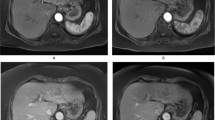

AIF—quality assessment

The score for the recirculation peak was significantly lower in group 1 compared to group 2 (p < 0.001) while the score for noise and artefacts was significantly higher with group 1 (p < 0.001). However, the total score for AIF quality was similar for the two groups (p = 0.818) (Table 3, Fig. 2). Inter-reader agreement was good for the total qualitative score (ICC = 0.88).

Example of AIF curves measured in the abdominal aorta with gadoxetate (a) and Gd-BOPTA (b) in two different patients with HCC. On the AIF curve with Gd-BOPTA, a recirculation peak is seen (arrow in b) while there was no visible recirculation peak with gadoxetate (arrow in a). Furthermore, the AIF curve with Gd-BOPTA shows minor noise and artefacts (arrowheads in b) while there was no irregularities related to noise and artefacts in the AIF curve with gadoxetate. Abbreviations: AIF, arterial input function; HCC, hepatocellular carcinoma; Gd-BOPTA, gadobenate dimeglumine; AU, arbitrary units; s, seconds

We found a similar overall quality score for AIF curves measured in the abdominal aorta with both contrast agents. However, the score was significantly lower for the recirculation peak of AIF curves and significantly higher for noise and artefacts for group 1 compared to group 2. Since the administered volume was the same for both contrast agents (0.1 mL/kg), the recirculation peak with Gd-BOPTA could be explained by the higher dose of administered gadolinium (0.05 mmol/kg) compared to gadoxetate (0.025 mmol/kg) which leads to a higher T1 relaxation rate in plasma [36]. Furthermore, the injection rate in group 1 was slower compared to that in group 2, which might have partially contributed to the differences in these parameters. Overall, we believe that both contrast agents are suitable for DCE-MRI with regards to AIF quality.